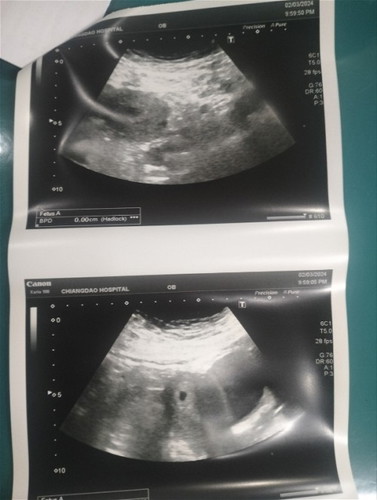

ท้องคนที่2

ขอคำปรึกษาษาหน่อยค่ะเจอถุงเเต่ไม่เห็นตัวอ่อน😓😓😓

คุณแม่รอน้องหน่อยนะคะอาจจะด้วยอายุครรภ์ที่น้อยมาก บ้านนี้ตอน 5+6 วีคก็ยังไม่เจอน้องค่ะ มาเจอเค้าอีกทีตอน8 วีค พยายามอย่าเครียดนะคะ

บ้านก็เปนค่ะ เจอถุงแต่ไม่เจอตัว คุณหมอให้ไปขูดมดลูกค่ะ แต่ของคุณแม่รอหมอนัดอีกทีนะคะ ะปนกำลังใจให้ค่ะ

เป็นเหมือนกันค่ะ หมอนัดอีกสองสัปดาห์ จับมือค่ะแม่

ไข่อาจตกช้าคะ รอดูไปก่อนสัก2-3วีค